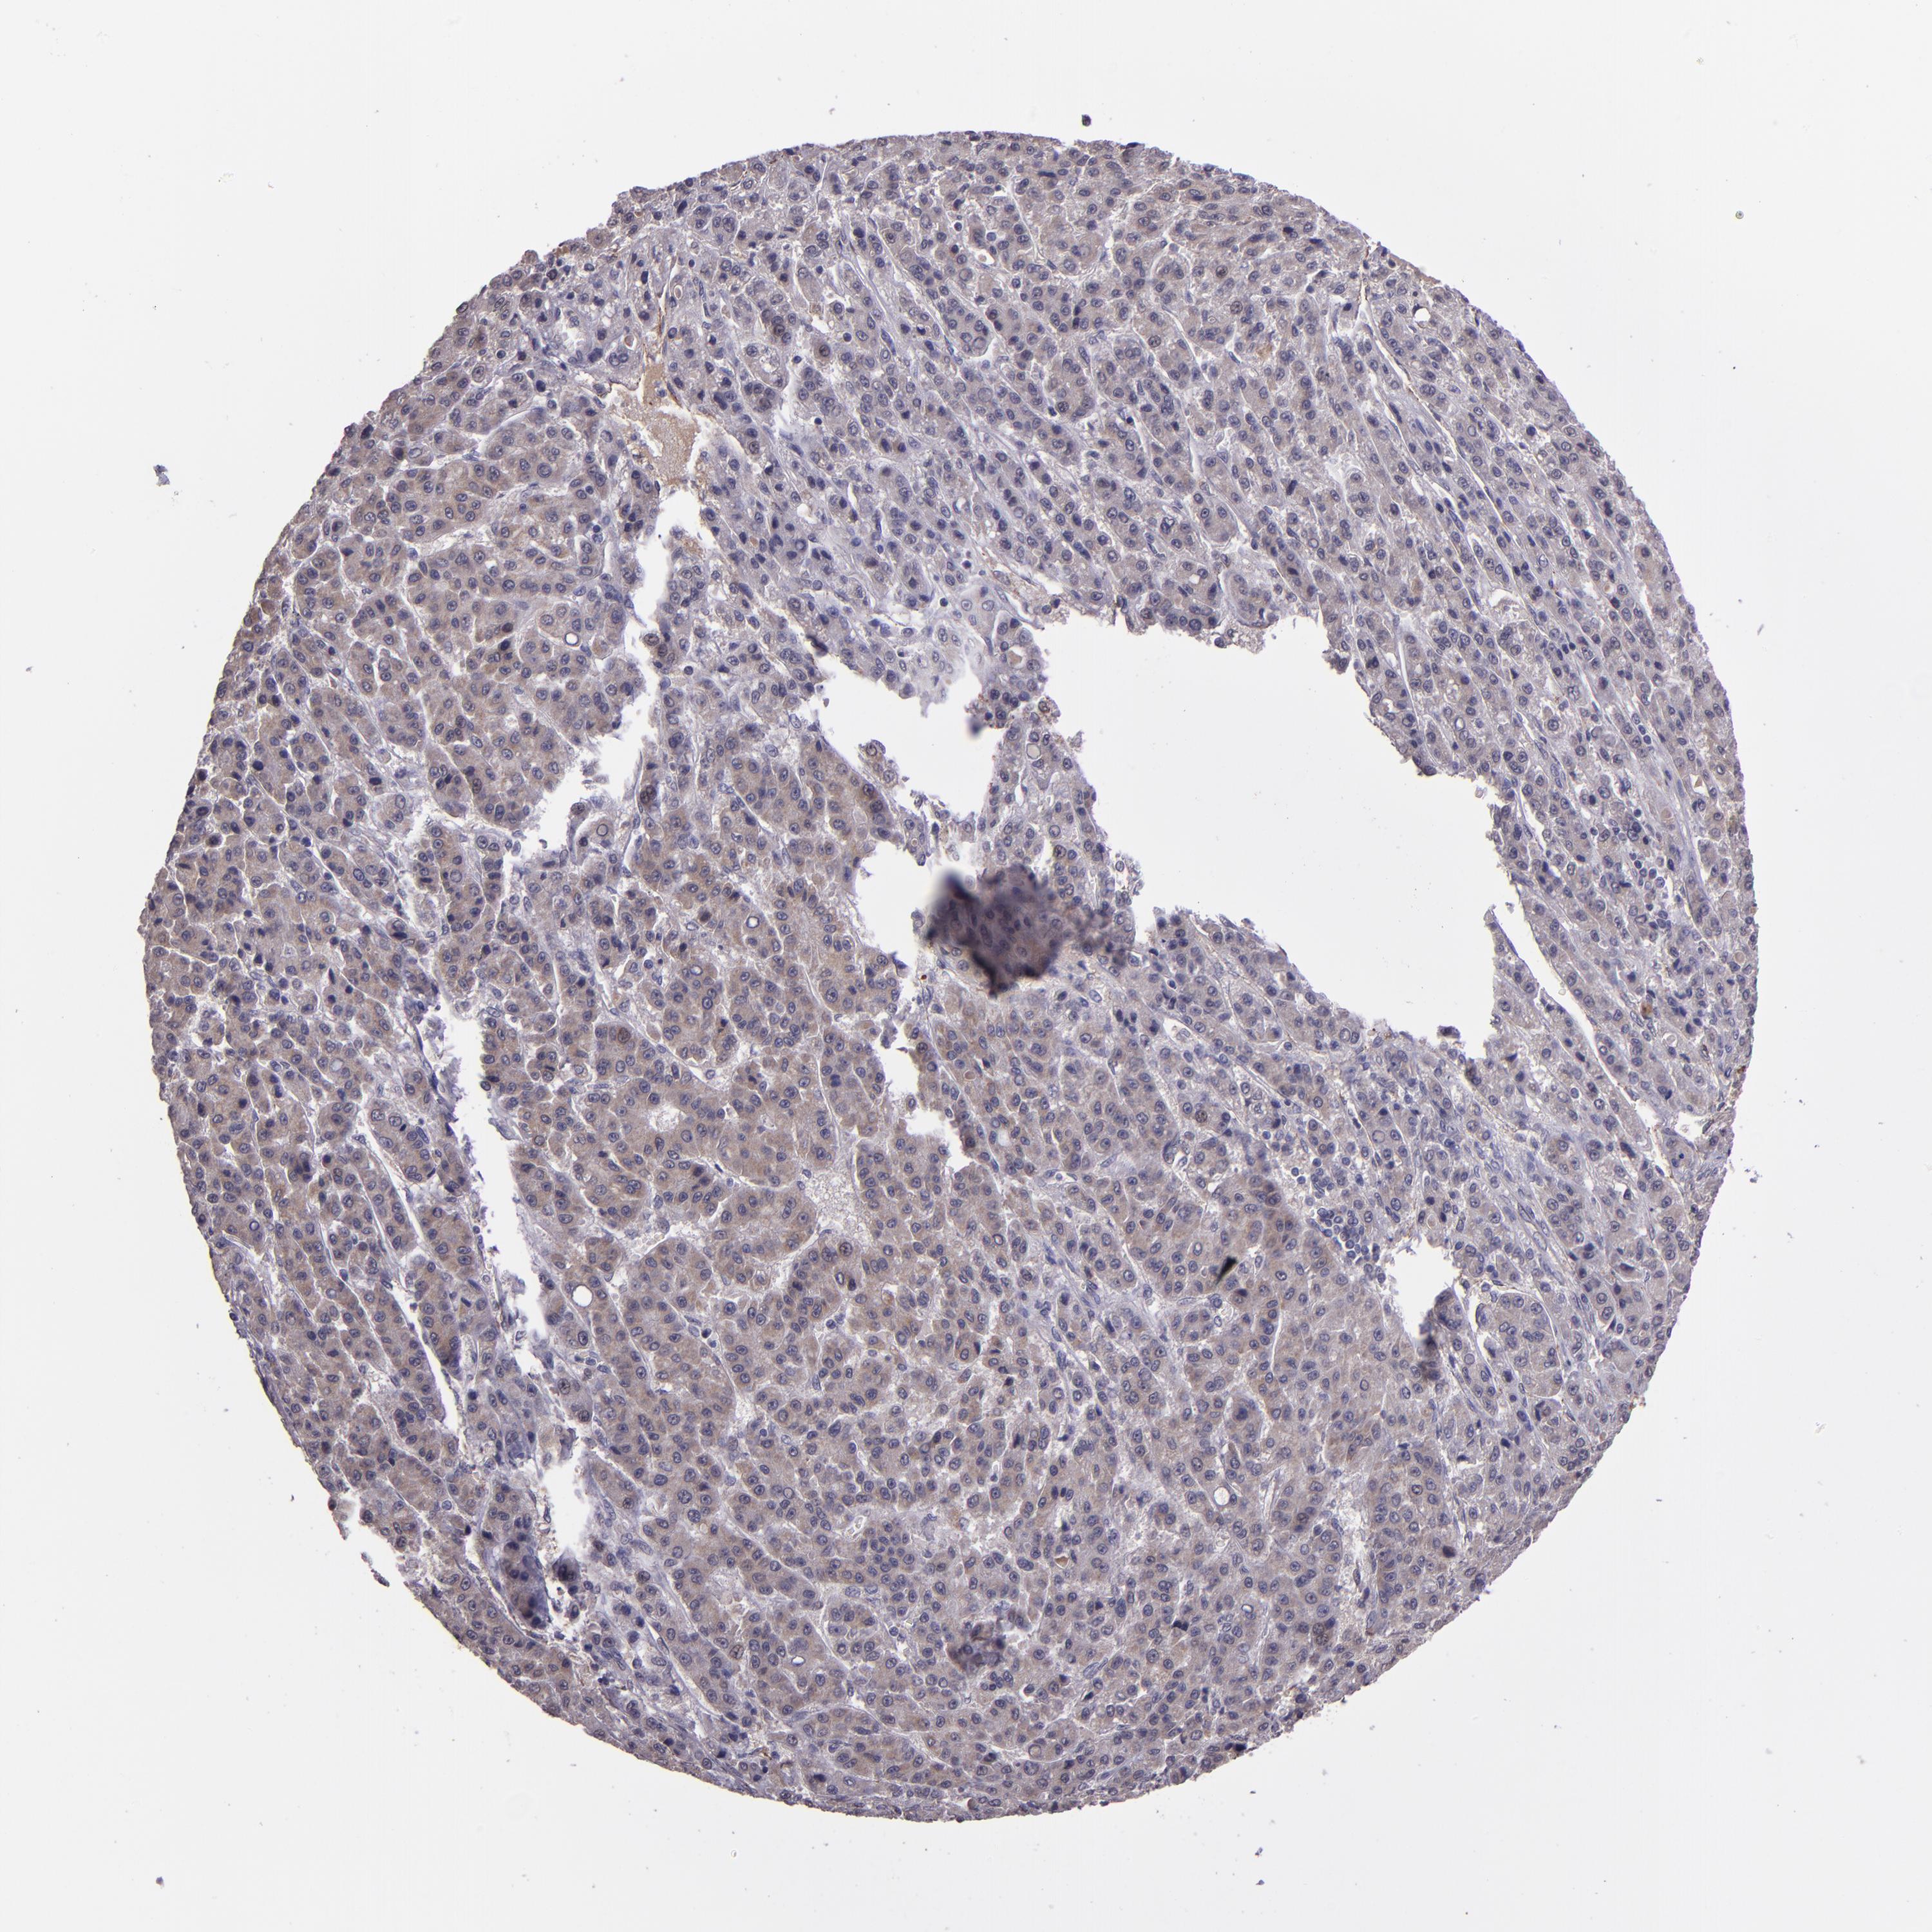

LIVER CANCER - Protein expressioni

A mouse-over function shows sample information and annotation data. Click on an image to view it in a full screen mode. Samples can be filtered based on level of antibody staining by selecting one or several of the following categories: high, medium, low and not detected. The assay and annotation is described here.

Note that samples used for immunohistochemistry by the Human Protein Atlas do not correspond to samples in the TCGA dataset.

Antibody stainingi

Antibody staining in the annotated cell types in the current human tissue is reported as not detected, low, medium, or high, based on conventional immunohistochemistry profiling in selected tissues. This score is based on the combination of the staining intensity and fraction of stained cells.

Each image is clickable and will lead to virtual microscopy that enables deeper exploration of all samples and also displays staining intensity scores, fraction scores and subcellular localization as well as patient and tissue information for each sample.

Antibody HPA001879

Staining

High

Medium

Low

Not detected

Intensity

Strong

Moderate

Weak

Negative

Quantity

>75%

75%-25%

<25%

None

Location

Nuclear

Cytoplasmic/membranous

Cytoplasmic/membranous,nuclear

Cholangiocarcinoma

Carcinoma, Hepatocellular, NOS